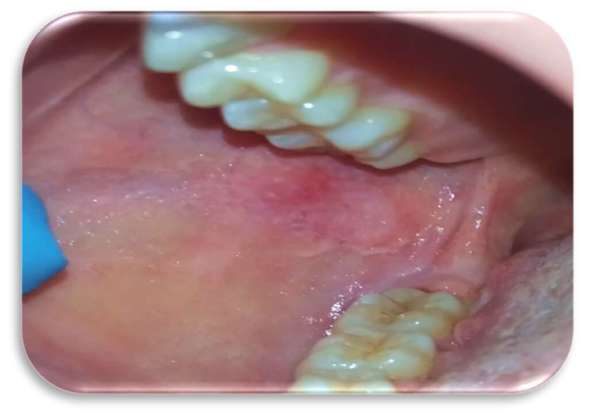

Inizialmente la paziente era stata trattata con collutorio a base di clorexidina 0,2% per circa 12 giorni senza alcun beneficio. Le lesioni si presentavano molto dolenti, erosive ed eritematose bilateralmente e simmetricamente sul ventre linguale (Figure 1 e 2) e sulla mucosa geniena, compatibili con un sospetto quadro clinico di lichen planus orale erosivo.

Sia sui margini linguali che sulle mucose geniene erano presenti, inoltre, segni di morsicatio buccarum e linea alba (Figure 3 e 4).